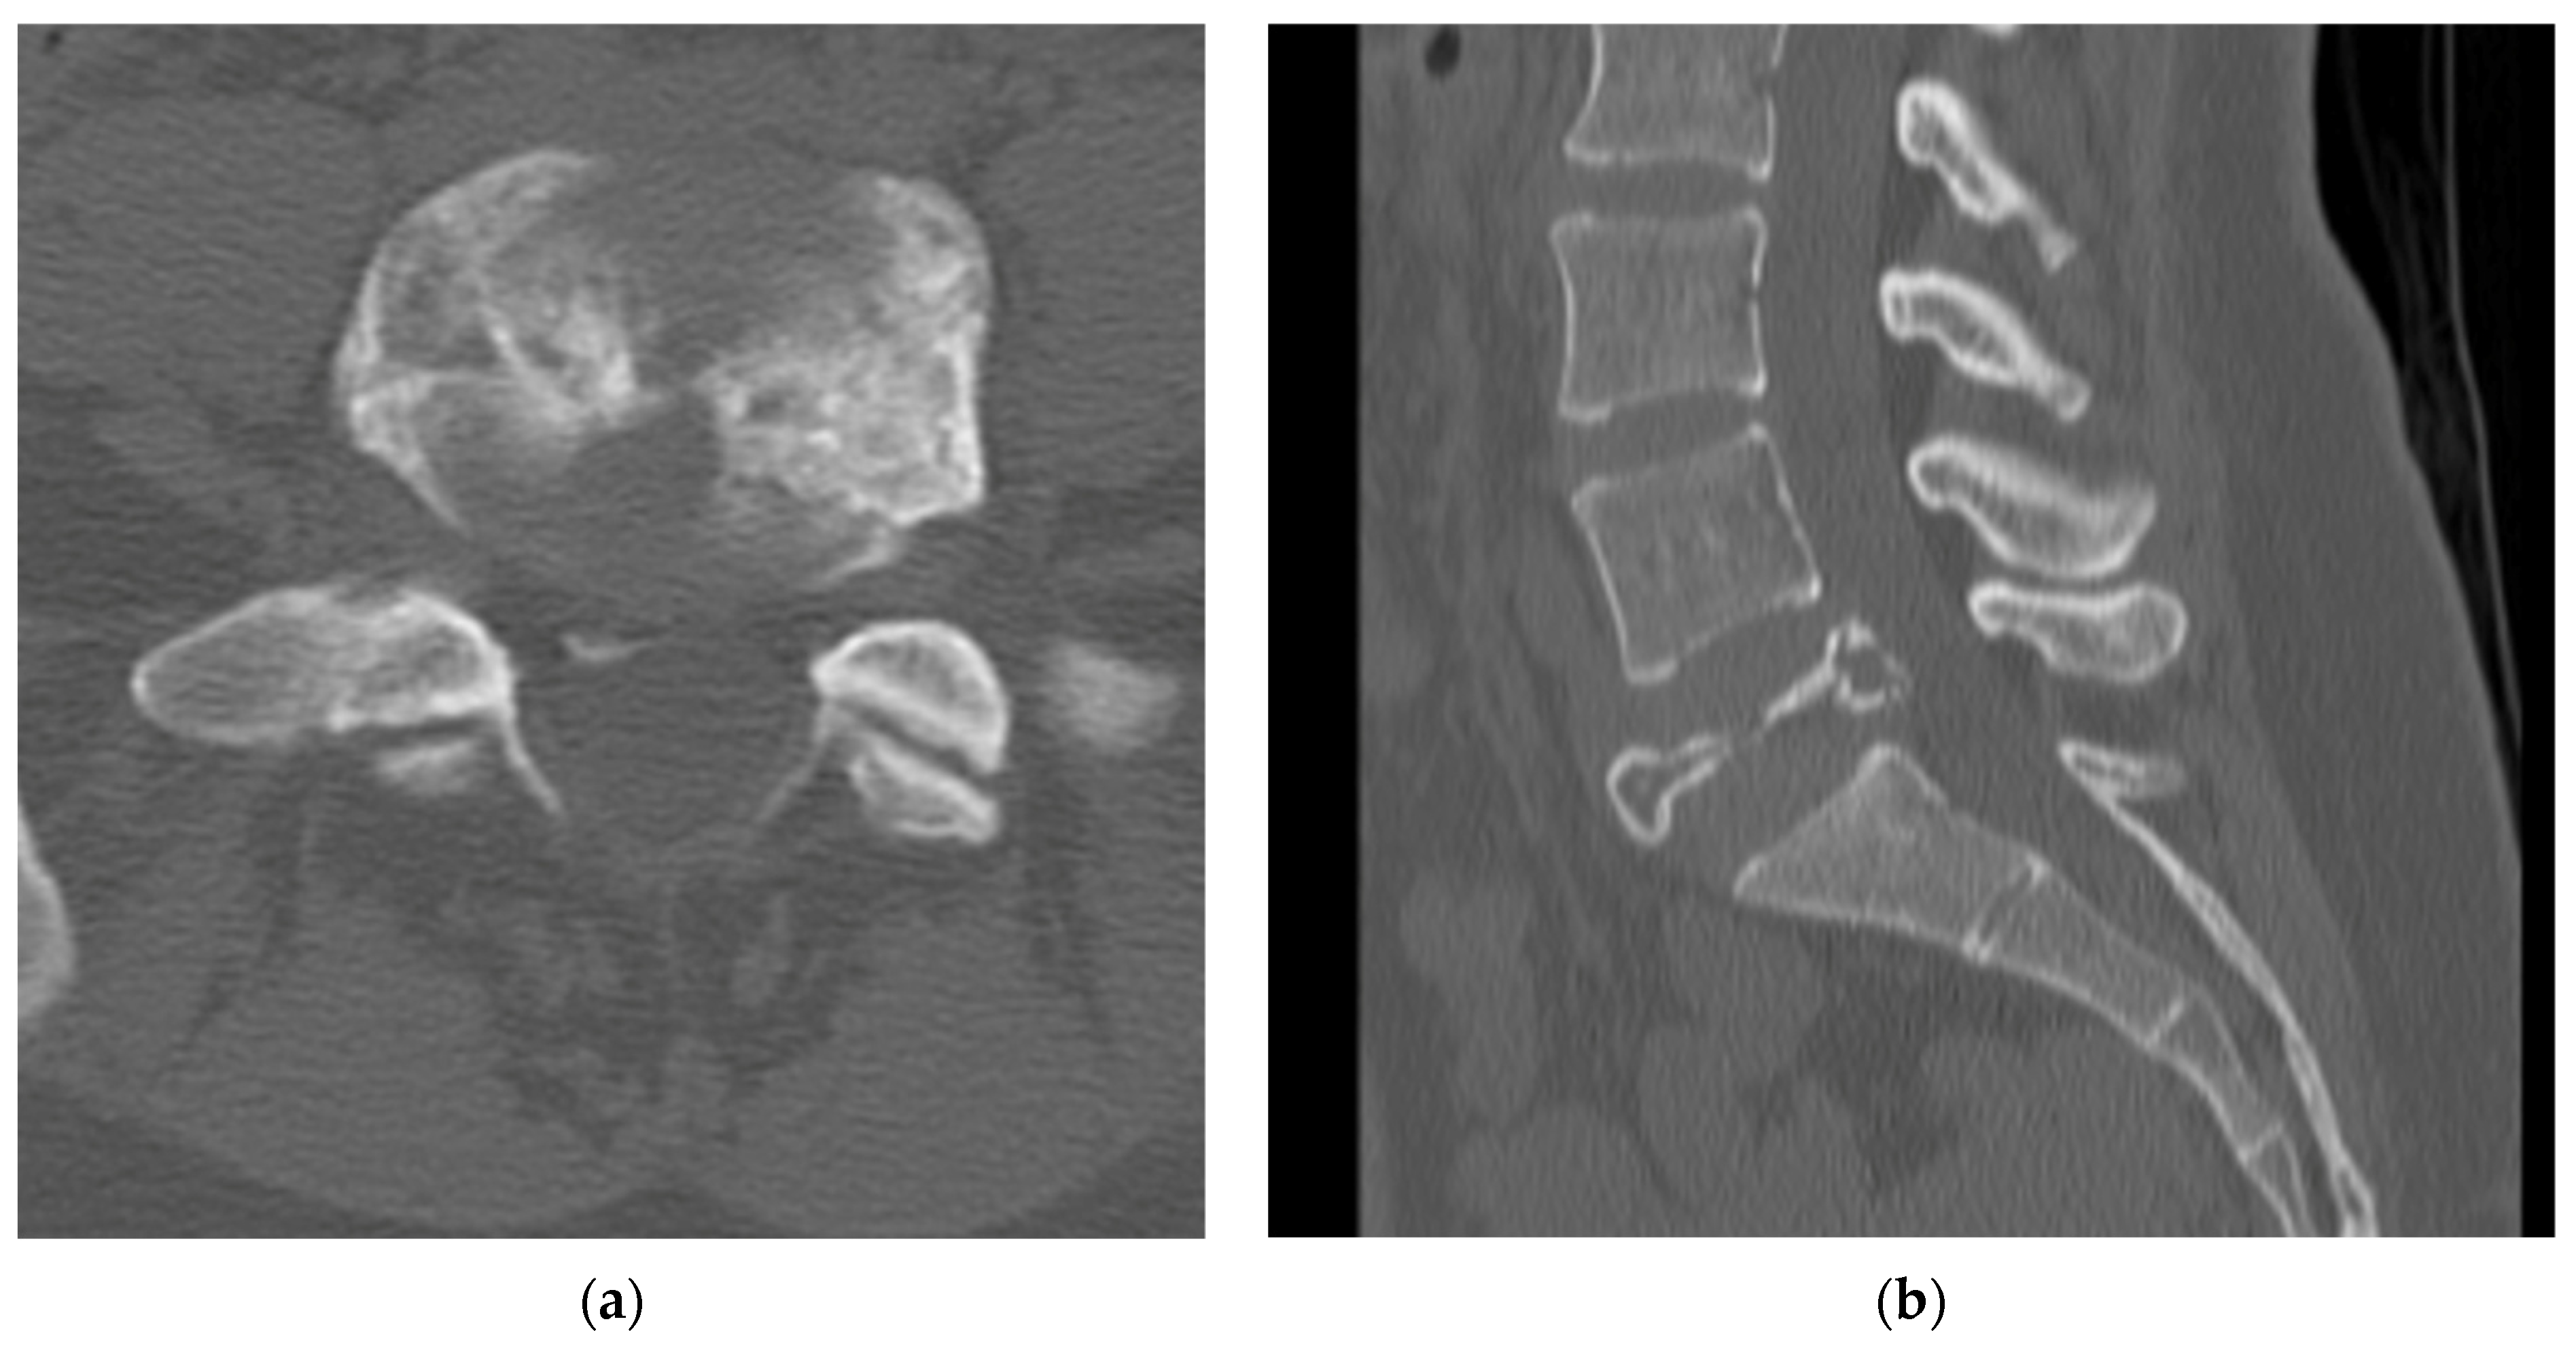

4.2.4. Computerized Tomography Scan